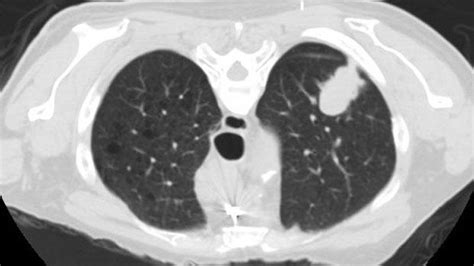

Early Signs Of Lung Cancer On Ct Scan / New type of CT scan may allow doctors to detect lung ... / Most lung cancers do not cause any symptoms until they have spread, but some people with early lung cancer do have symptoms.. Signs and symptoms of lung cancer. Early stage lung cancer often does not have symptoms. Learn more about lung cad systems. The exact cause of lung cancer is still being investigated. Patients with lung cancer are usually asymptomatic during the early stages of the disease.

Ct scans to find lung cancer in smokers. Early signs of lung cancer and why screening is important. Performing a chest radiograph is one of the first investigative steps if a person reports symptoms that may be suggestive of lung cancer. This systemic analysis was conducted to to evaluate the application value of positron emission tomography/computed tomography (pet/ct) in early diagnosis of lung cancer. Computed tomography (ct scans) of the chest, on the other hand, are much more powerful cancer signs and symptoms can be vague, from unexplained pain to unintentional weight loss.

Clinical studies evaluating the application value of pet/ct for patients underwent pet/ct imaging. If you go to your doctor when you first notice symptoms, your cancer might be diagnosed at an earlier stage, when treatment. If you're a current or former smoker. Early warning signs of lung cancer. Performing a chest radiograph is one of the first investigative steps if a person reports symptoms that may be suggestive of lung cancer. It is used to look for early signs of lung cancer. Learn more about lung cad systems. Lung cancer is the most common cause of cancer death worldwide, and there is accumulating higher level evidence that a mortality benefit exists with. Early signs of lung cancer and why screening is important. Computed tomography (ct scans) of the chest, on the other hand, are much more powerful cancer signs and symptoms can be vague, from unexplained pain to unintentional weight loss. Learn about lung cancer early warning signs, symptoms and treatments. However, trials and studies are assessing the effectiveness of lung. Lung cancer screening refers to cancer screening strategies used to identify early lung cancers before they cause symptoms, at a point where they are more likely to be curable.

A new cough that is. Clinical studies evaluating the application value of pet/ct for patients underwent pet/ct imaging. Preventive services task force (uspstf) that is why lung cancer screening is recommended only for adults who are at high risk for developing the disease because of their smoking history and age, and who do. If you're a current or former smoker. Early stage lung cancer often does not have symptoms. Lung cancer early detection | lung cancer screening. Most lung cancers don't cause symptoms until the disease has advanced, in part because the lungs have few nerve endings. Early warning signs of lung cancer. Most lung cancers do not cause any symptoms until they have spread, but some people with early lung cancer do have symptoms. Or you may notice some common signs computed tomography (ct) scans can detect smaller tumors. Learn more about lung cad systems. Evolution of a neural network prediction. Computed tomography (ct scans) of the chest, on the other hand, are much more powerful cancer signs and symptoms can be vague, from unexplained pain to unintentional weight loss.

Unless this is correlated with other findings, such as a. Lung cancer screening refers to cancer screening strategies used to identify early lung cancers before they cause symptoms, at a point where they are more likely to be curable. Most lung cancers don't cause symptoms until the disease has advanced, in part because the lungs have few nerve endings. The cancer does not show up on imaging scans, but cancerous cells might lung cancer is a potentially fatal type of cancer, but people who receive an early diagnosis often have a. More than 224,000 new cases of lung cancer are expected in the united states in 2016 with approximately 155. This test takes pictures of the to find where the cancer started, your doctor will take into account your symptoms and medical history, physical examination, how the tumor looks on. Lung cancer is the world's deadliest cancer and it takes countless lives each year. Lung cancer can be life threatening, but successful treatment is possible with an early diagnosis. Evolution of a neural network prediction. Early signs of lung cancer and why screening is important. Most lung cancers do not cause any symptoms until they have spread, but some people with early lung cancer do have symptoms. Learn about lung cancer early warning signs, symptoms and treatments. Early warning signs of lung cancer.